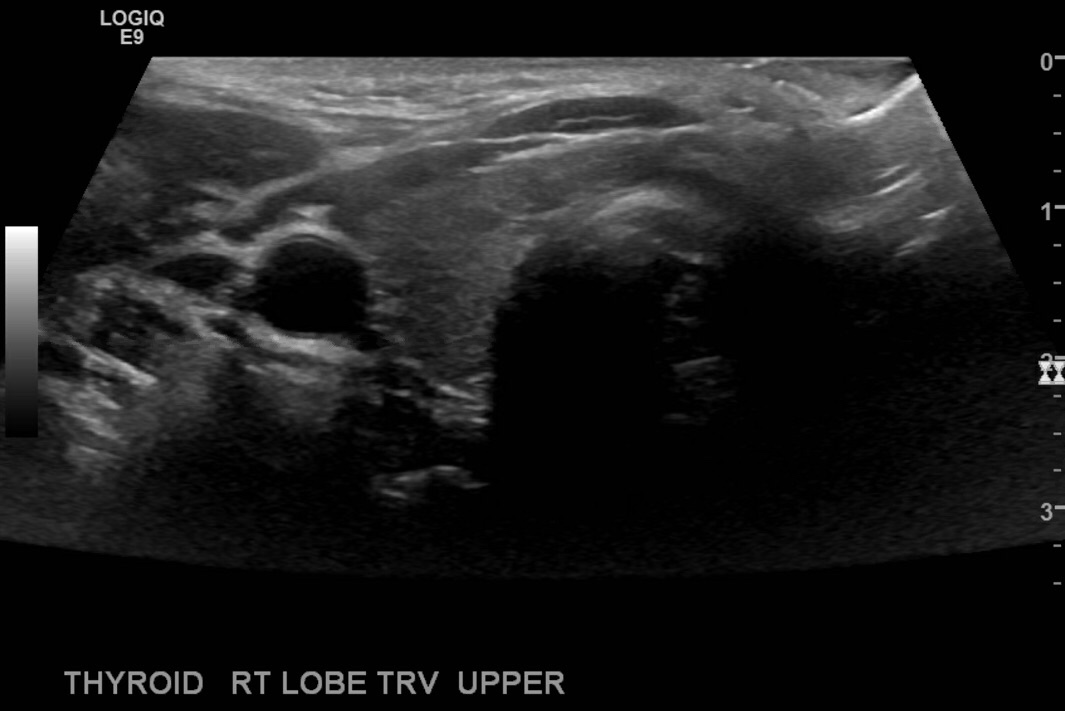

Turn the transducer counterclockwise and take transverse images at the middle of the rt lobe, superior and inferior.